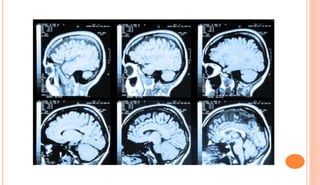

MRI